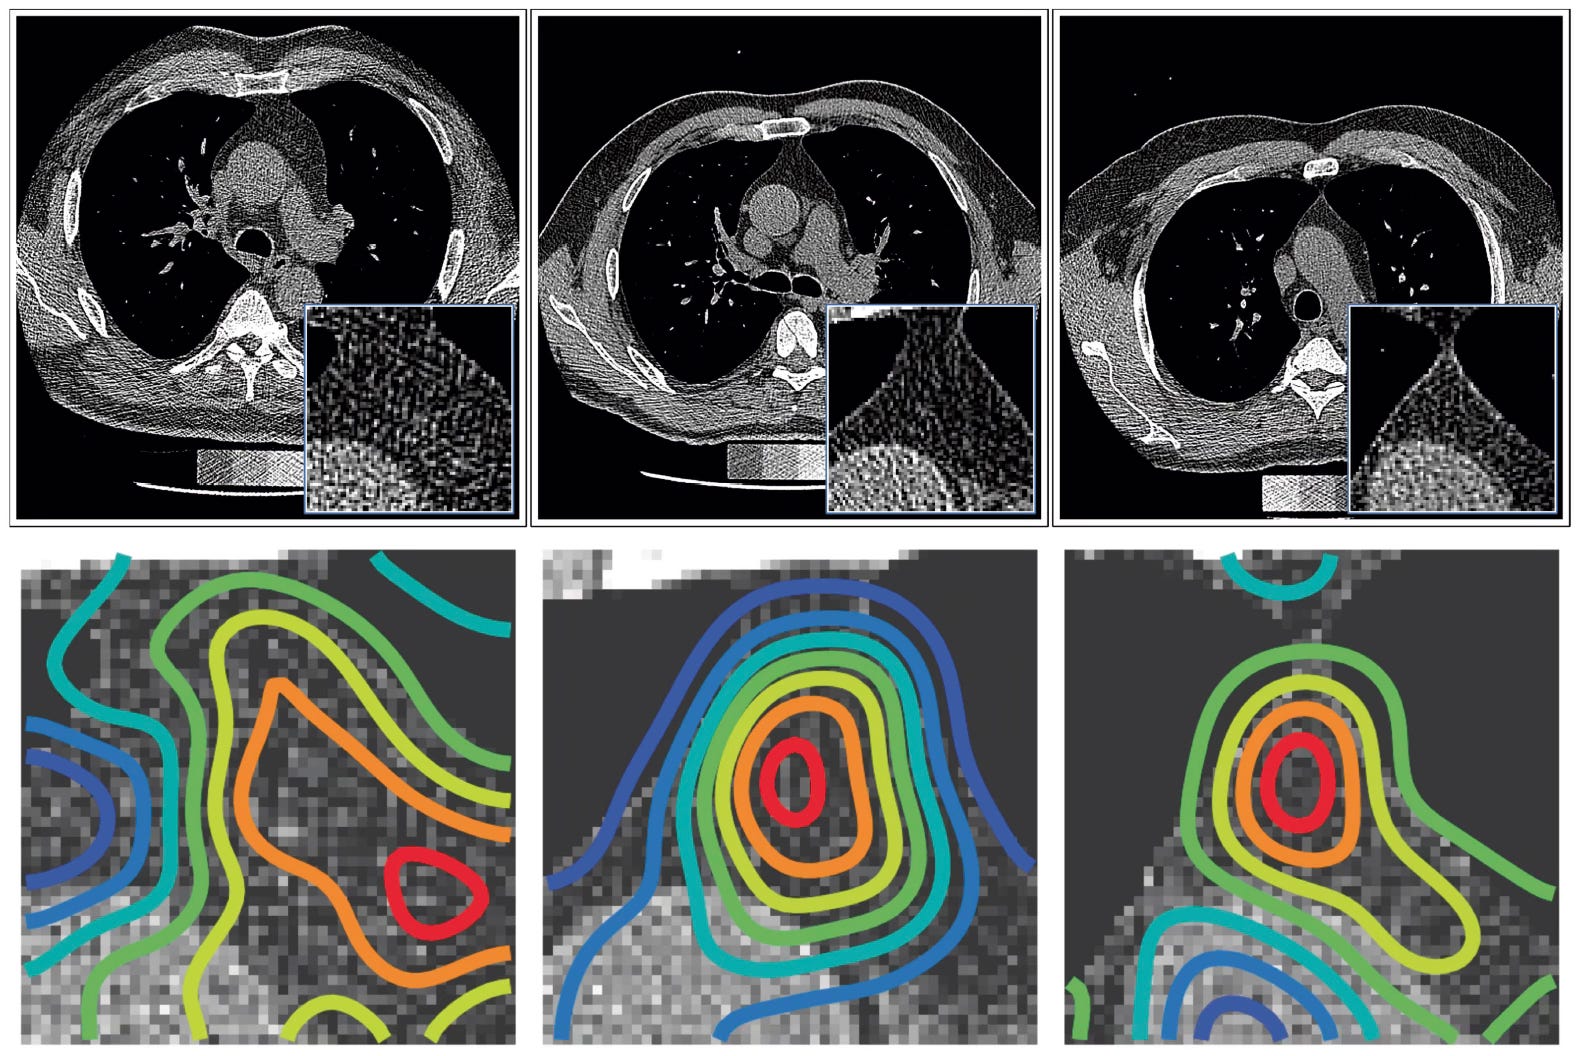

Below are a few saliency maps from the occlusion sensitivity that indicate the thymic bed focus, not affected by neighboring structures, using the jet color scale.